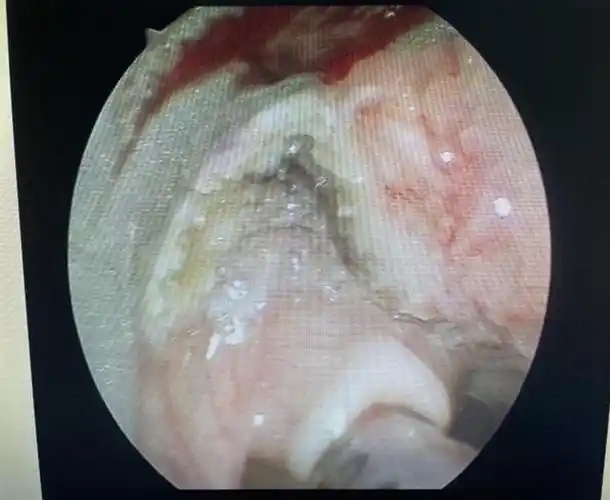

2岁女童喉咙里长满肿瘤1年经历12次手术

真如鲠在喉济一2个月小孩嗓子里长了巨大肿瘤

男子咽喉不适,声音嘶哑,以为是咽炎,谁知竟是16cm肿物"封喉"!